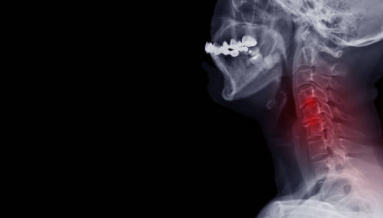

안녕하세요, 여러분! 오늘은 많은 사람들이 겪고 있는 '목디스크'에 대해 자세히 알아보려고 해요. 목디스크는 우리 목의 척추 사이에 있는 디스크가 튀어나와 신경을 압박하면서 생기는 질환인데요. 갑자기 목이 아프거나 어깨가 뻐근할 때, “혹시 나도 목디스크?”라는 생각이 들 수도 있어요. 그래서 이번 글에서는 목디스크의 주요 증상 10가지를 하나씩 살펴보면서, 몸의 신호를 잘 이해할 수 있도록 쉽게 설명해 드릴게요.

먼저, 목디스크가 무엇인지부터 짚고 넘어가야겠죠? 목디스크는 우리 목에 있는 척추뼈 사이에 있는 디스크, 즉 쿠션 역할을 하는 연골조직이 제자리에서 벗어나 신경을 눌러 생기는 질환이에요. 마치 오래된 베개 속 솜이 한쪽으로 쏠려서 불편해지는 것처럼, 목디스크도 비슷한 이유로 문제를 일으켜요. 디스크가 제자리에 있지 않으면 신경을 자극해서 통증을 유발하고, 심할 경우에는 팔 저림이나 두통까지 나타날 수 있답니다.